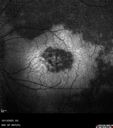

Choroidal hemangioma 10 year old black male11 views10 year old black child The patient has been wearing glasses which for 3 years and the left eye has had a changing prescription.

3/13/23: OD: +1.00; OS: +5.50

7/18/24: OD: +1.00; OS: +8.00 -1.25 x 015

2/3/25: (Cycloplegic): OD: +2.00; OS: 11.50+1.50 x 120

She had an MRI scan was not diagnostic.

VA OD:20/16

OS: 20/30-2

B-scan 5.1 mm H x 12.3 mm A x 15.0 mm T highly reflective mass centered just temporal to the macula involving the entire macula).

Seen at Wills and observation was decided because of no macular fluidAug 13, 2025